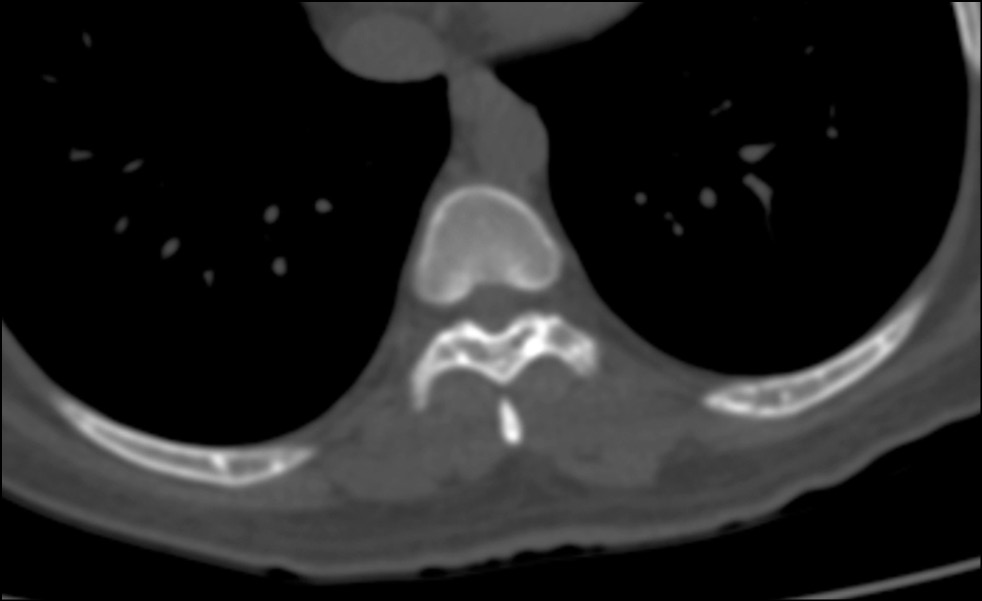

A 43-year-old female patient was taken to the emergency room by ambulance after experiencing transient loss of consciousness. The initial evaluation consisting of history, physical examination, 12-lead electrocardiogram and laboratory tests did not reveal any abnormalities; thus, a total-body computed tomography (CT) was performed. The CT scan showed multiple small sclerotic foci bone islands, scattered throughout the thoracic (Figure 1a) and lumbar spine (Fig. 1b), ribs, pelvic bone (Fig. 2), sacrum (Fig. 3) and bilateral proximal femur (Fig. 4). All bones were free of any cortical erosion or periosteal reaction. No other signs, such as rubor or edema, were noticed; moreover, the patient did not describe any numbness, tingling and weakness in the legs or other parts of the body.

Fig. 2. Transverse cross-section computed tomography scan passing through the seventh rib. It shows numerous hyperdense lesions; these are well-circumscribed and are measured in millimeters.